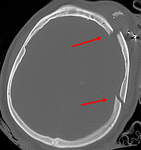

Linear parietal fracture without depression

From the teaching collection of Demetrios Demetriades; used with permission